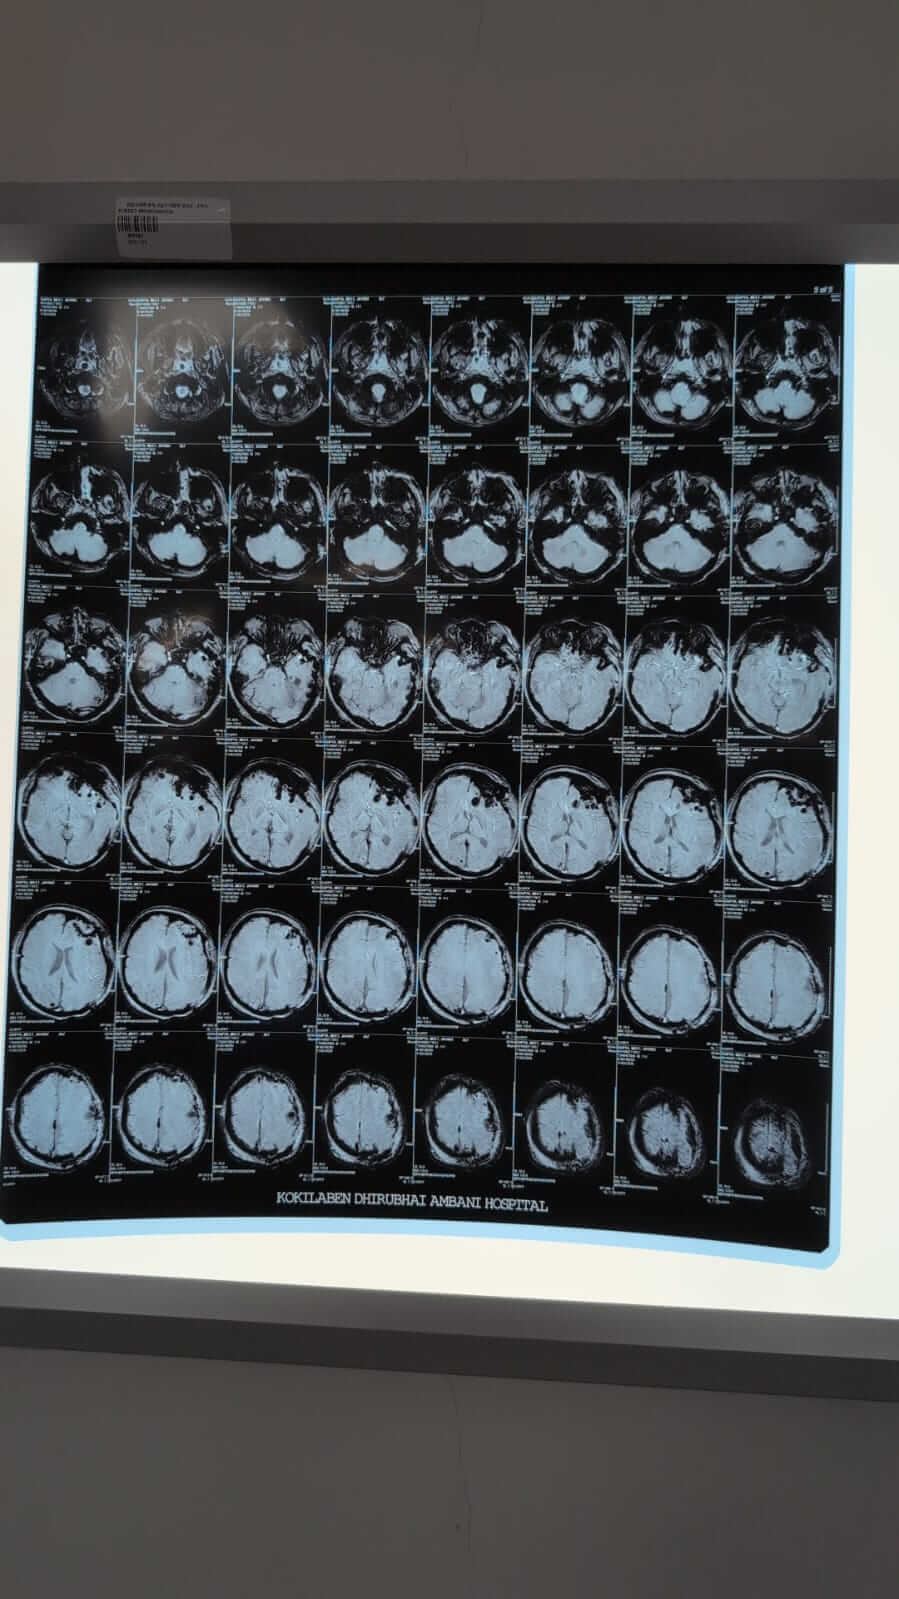

I still can’t process how one normal day turned into this. My brother Meet was just coming back home from college, and then one phone call changed everything. They said he fell from a moving train at Andheri. When I saw him in the hospital, he didn’t look like the same person. His head was badly injured, and doctors had to rush him for brain surgery to control the swelling and remove a blood clot.

Those hours felt endless. Even now, he hasn’t opened his eyes yet, but I hold onto every small sign, the way his fingers move, the slight movement in his legs, his lips trying to say something. He’s breathing on his own now, and the doctors say the swelling has reduced, but he still has a long way to go.